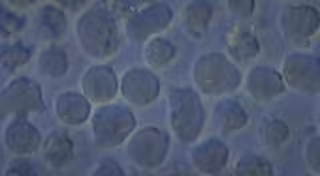

Células de una leucemia aguda de tipo B, enfermedad contra la cual ha demostrado eficacia el tratamiento con células CAR-T.

Células de una leucemia aguda de tipo B, enfermedad contra la cual ha demostrado eficacia el tratamiento con células CAR-T. - INSTITUTO DE INVESTIGACIÓN LEUCEMIA JOSEP CARRERAS